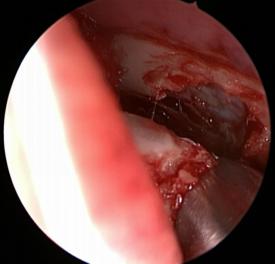

打開骨壁,暴露淚囊